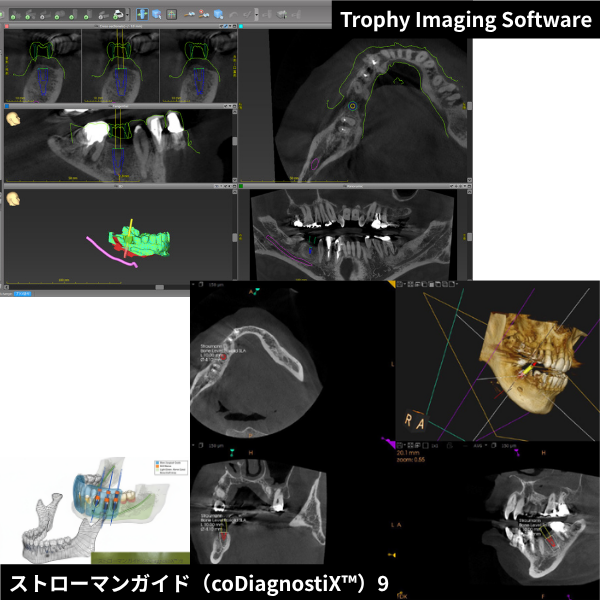

CT

手術の安全性と精度を高めるため、当院ではCTスキャンを活用しています。インプラント治療は、人工の歯根(インプラント体)をあごの骨に埋め込む治療です。あごの骨には神経や血管が通っているため、これらを傷つけないよう慎重な計画が必要です。

CTスキャンは、一般的な二次元レントゲンとは異なり、骨の構造を三次元で確認できるため、あごの骨内の神経や血管の正確な位置を把握することが可能です。これにより、より正確で安全な治療計画を立てることができます。

シミュレーションソフト

CTスキャンで取得した詳細なデータをコンピュータに取り込み、専用のシミュレーションソフトで綿密に解析します。

この解析により、インプラントの最適な大きさ、正確な埋入位置、適切な埋入角度を判断し、術前に具体的な手術計画を立てます。

インプラントガイド

インプラントガイドは、インプラント治療を「正確」「安全」「スムーズ」行うための重要なサポートツールです。

手術時にインプラントを埋入する深さや角度を正確にナビゲーションしてくれます。このガイドに基づいて手術を行うことで、 人為的な誤差を大幅に減らすことができます。

2つの3Dシミュレーション

2つの3Dシミュレーションソフトを使用し、多角的、立体的に準備を進めます。当院では、経験豊富な設計のプロと一緒に万全のインプラント設計計画を立てており、可能な限り事前に患者様への不安と取り除くよう努めております。

ガイドシステム採用

顎骨は細いため、角度により顎骨からインプラント先端が出ることがあります。当院ではガイドシステムを採用しているため、経験や勘に頼らない精密な手術が可能です。その結果、口腔内の傷口も最小限のとどめることができ、術後のダウンタイムも少なく済みます。

ガイドシステム採用

顎骨は細いため、角度により顎骨からインプラント先端が出ることがあります。当院ではガイドシステムを採用することにより、経験や勘に頼らない、精密な手術ができることのより、口腔内の傷口も最小限のとどめる為術後のダウンタイムが少なく済みます。